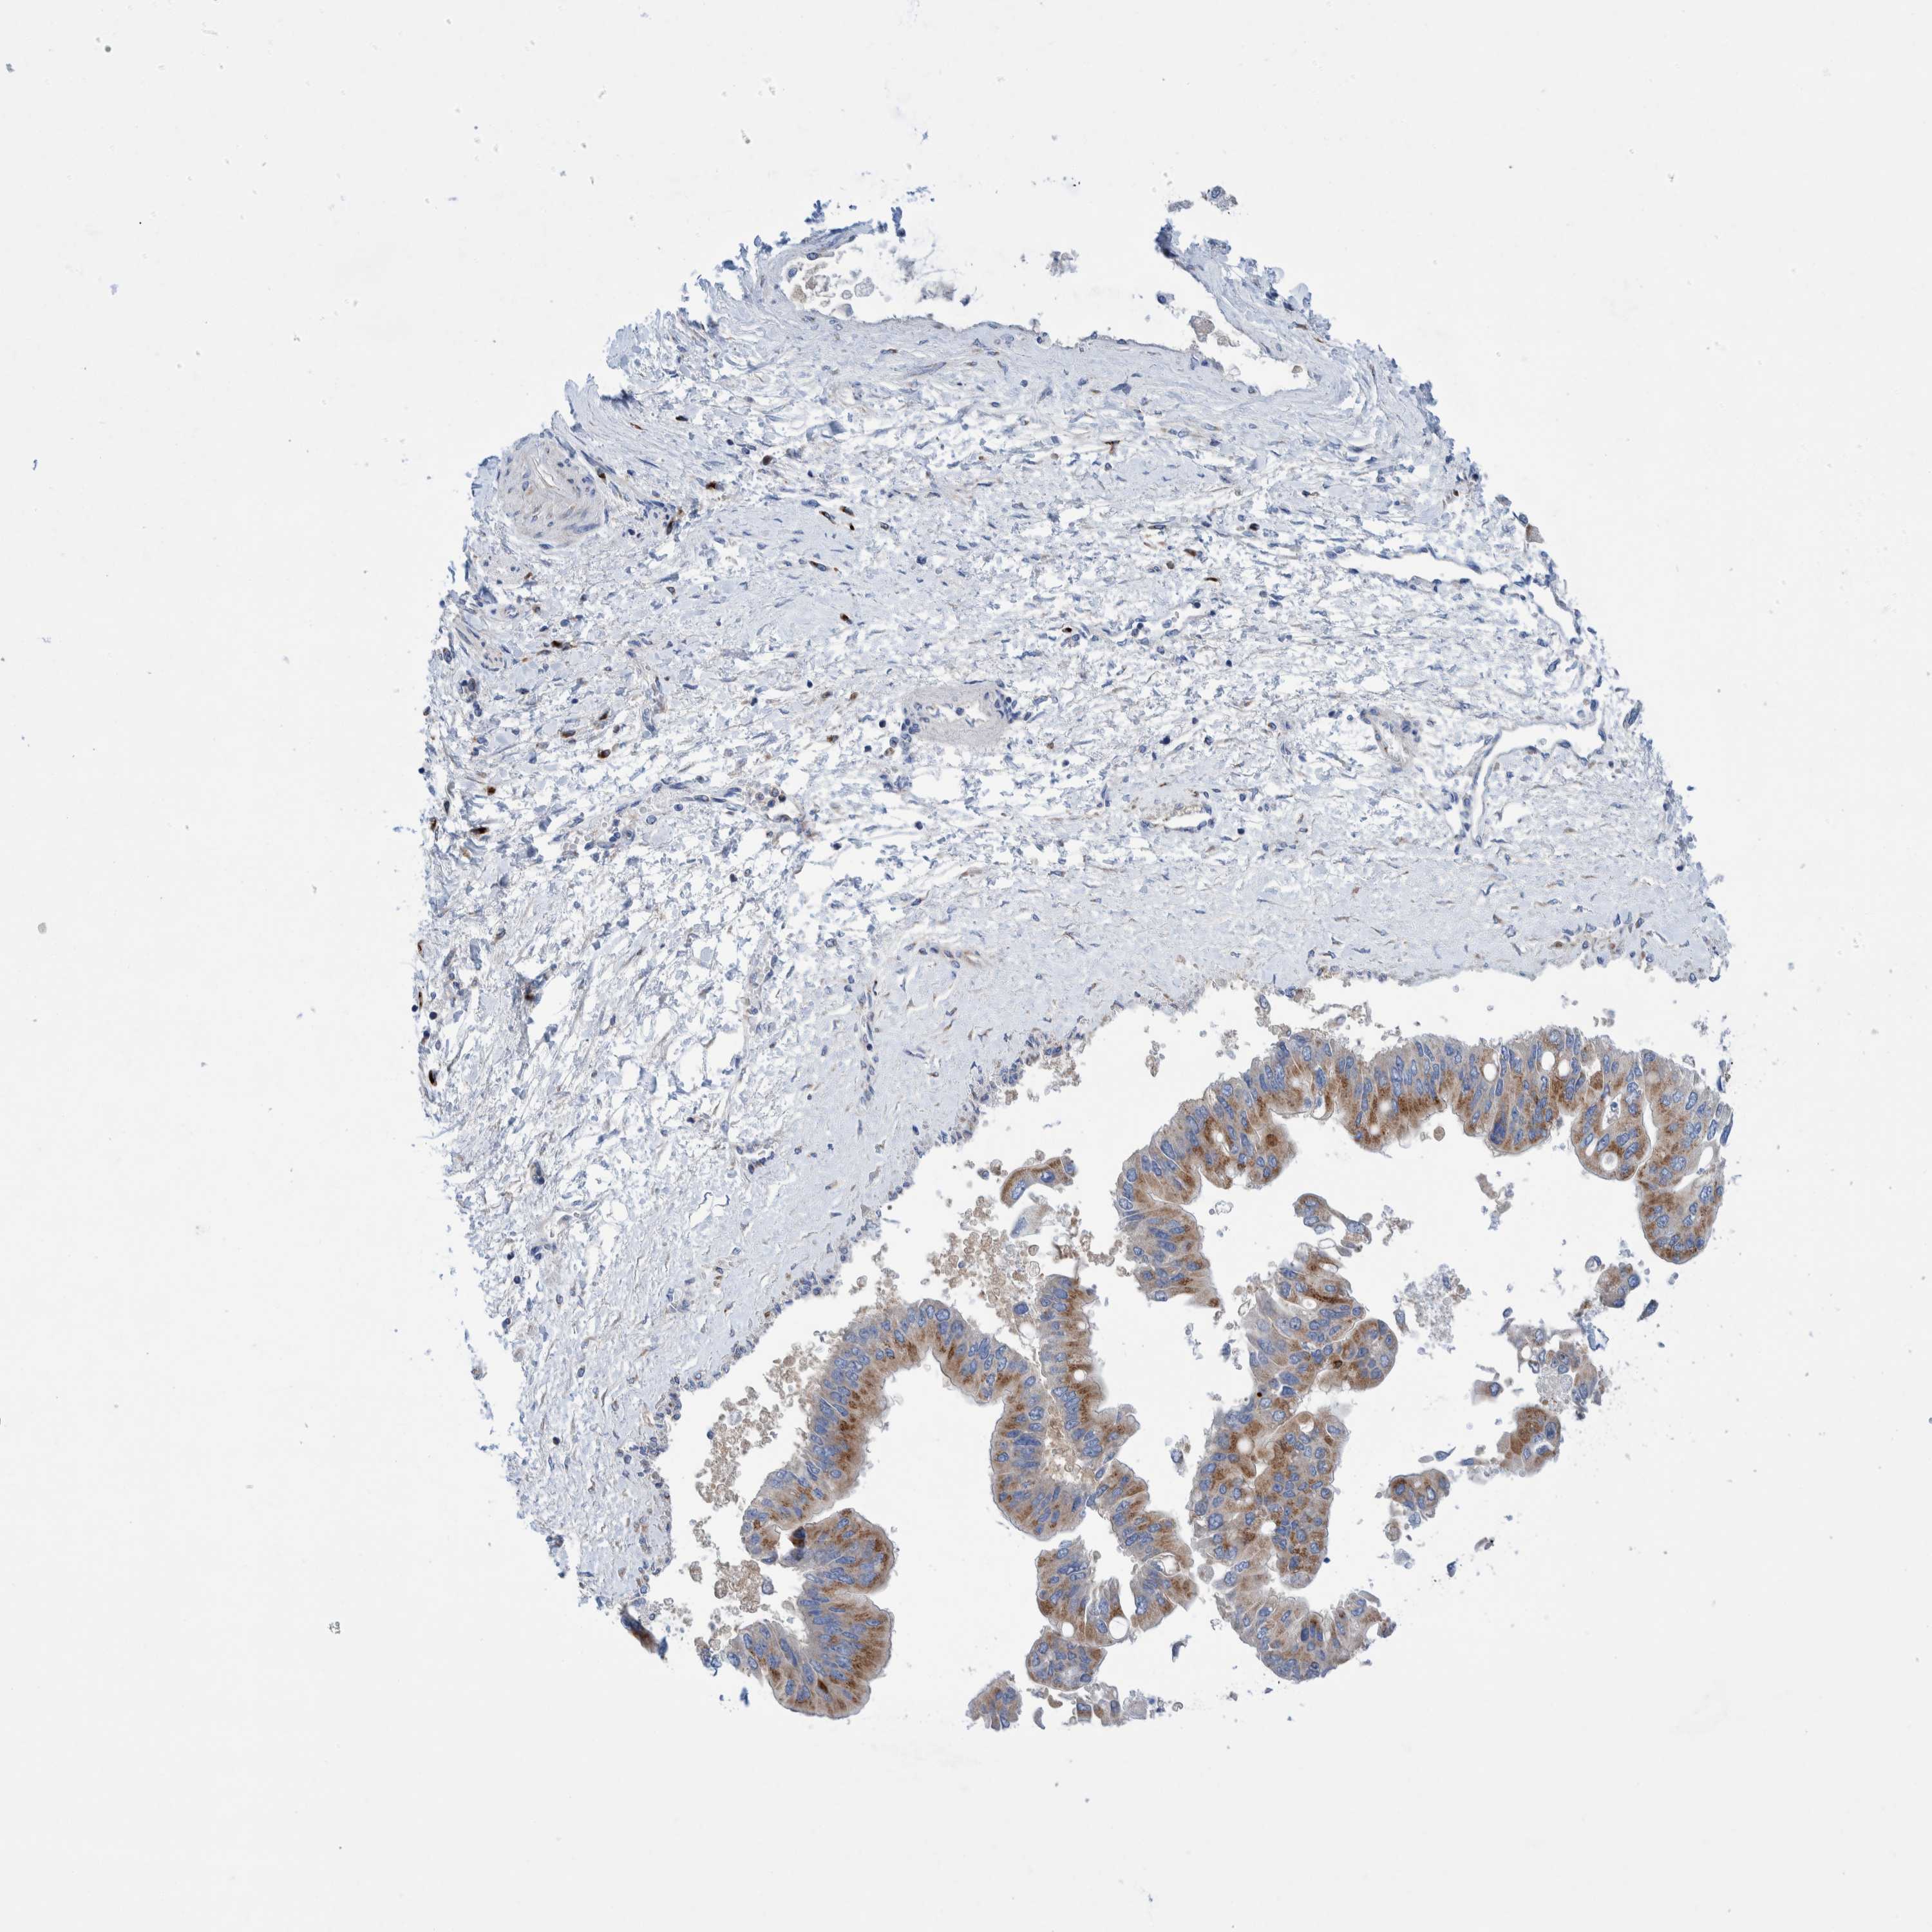

LIVER CANCER - Protein expressioni

A mouse-over function shows sample information and annotation data. Click on an image to view it in a full screen mode. Samples can be filtered based on level of antibody staining by selecting one or several of the following categories: high, medium, low and not detected. The assay and annotation is described here.

Note that samples used for immunohistochemistry by the Human Protein Atlas do not correspond to samples in the TCGA dataset.

Antibody stainingi

Antibody staining in the annotated cell types in the current human tissue is reported as not detected, low, medium, or high, based on conventional immunohistochemistry profiling in selected tissues. This score is based on the combination of the staining intensity and fraction of stained cells.

Each image is clickable and will lead to virtual microscopy that enables deeper exploration of all samples and also displays staining intensity scores, fraction scores and subcellular localization as well as patient and tissue information for each sample.

Antibody HPA023637

Staining

High

Medium

Low

Not detected

Intensity

Strong

Moderate

Weak

Negative

Quantity

>75%

75%-25%

<25%

None

Location

Nuclear

Cytoplasmic/membranous

Cytoplasmic/membranous,nuclear

Cholangiocarcinoma

Carcinoma, Hepatocellular, NOS